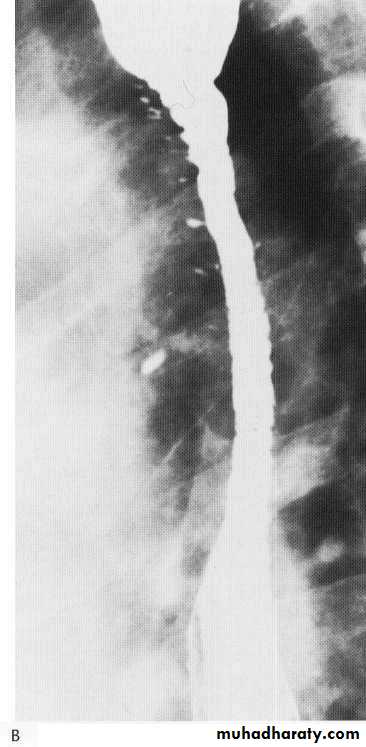

Advanced esophageal Ca